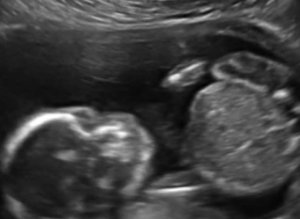

أظهرت لقطات فيديو تمّ بثها على الشبكات الاجتماعية جنيناً يوجّه لكمات لوجهه في حركة مفاجئة أثارت استغراب والديه والطاقم الطبي.

كان الزوجان الأميركيان ديف وفينيسا يجريان فحصاً دورياً للأسبوع العشرين من حمل فينيسا الأول بعد عامين من الزواج حين مرّا بالتجربة المفاجِئة، وفق ما ذكرته صحيفة "مترو" البريطانية، الاثنين 8 فبراير/شباط 2016.

وعلّق ديف بقوله: "لقد كانت صدمةً حقيقية، كنا نشاهد حركة الجنين أثناء فحص الموجات فوق الصوتية، وفجأة حدث هذا. ضحكنا وضحكت الممرضة وقالت إنه مشهدٌ جديد بالنسبة لها".